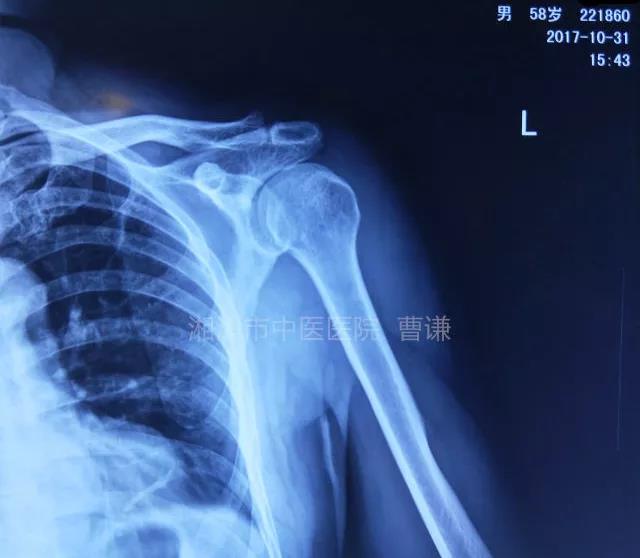

当地接诊医生应该说还是很负责的,同时拍了健侧片对比:

影像科报告,骨科医生光看报告行吗?